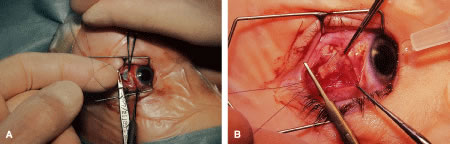

RECESSION PROCEDURE: FORNIX INCISION

This procedure is recession of the right medial rectus muscle. The eyelids are separated with a Barraquer open-blade wire eyelid speculum (Fig. 8). The open-blade design provides more room for exposure and makes it easier to pass the suture needles, especially in small children or when large recessions are performed. The globe is grasped with a Lester forceps at the limbus. It is best to grasp the limbus with the forceps held perpendicular to the globe and then to position the forceps so that they are rotated and lie tangential to the globe. Forced ductions are performed to detect any restriction of movement of the globe (Fig. 9).

Fig. 8. The lids are separated with a Barraquer open-blade wire speculum. The eye is abducted to test for restriction.

Fig. 9. A Lester forceps grasps the limbal conjunctiva to perform a forced duction test. Care is taken not to allow the globe to move posterior during this maneuver. Restriction of globe rotation should be recorded, and, if it is significant, adjustments in the surgical procedure may be considered.